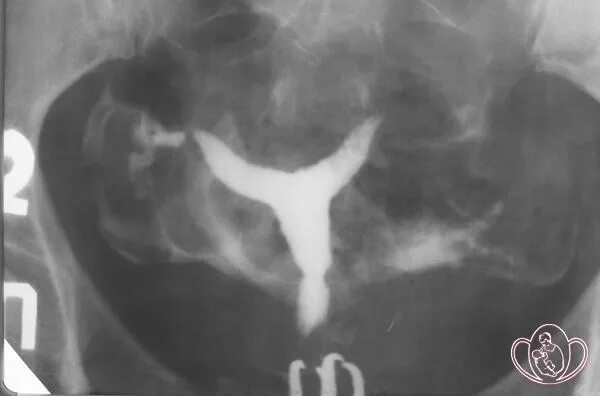

Что такое две матки у женщины